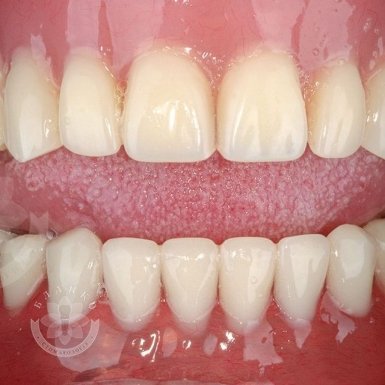

Зубная имплантация — это современное и надежное решение для восстановления утраченных зубов. В стоматологической клинике Бланко мы предлагаем имплантацию зубов «под ключ», что означает полный комплекс услуг — от диагностики до установки коронки, без скрытых платежей и неожиданных расходов.

🔹 Полный цикл услуг – от первичной консультации до финальной установки зуба.